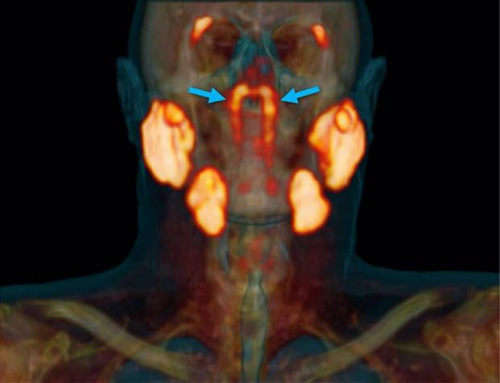

قسمتهای نارنجی رنگ عکس بالا سایر غدههای بزاقی سر هستند و بخشی که با فلشهای آبی نشان داده شده، همان عضو جدید و مرموز بدن است. وتر ووگل (Wouter Vogel) از موسسه سرطان هلند میگوید که بدن انسان شامل سه جفت غده بزاقی بزرگ میشود، اما هیچکدام از این جفتها در پشت قسمت بالایی حلق قرار ندارند.

تمامی اینها در حالی بوده که ووگل و تیمش از وجود یک جفت چهارم از غدههای بزاقی در پشت بینی و بالای سقف دهان، نزدیک به مرکز سر انسان خبر میدهند. جفتی که تاکنون وجود آن توسط هیچ دانشمندی کشف نشده بود و با در نظر گرفتن قرنها پیشرفت چشمگیر علم پزشکی و آناتومی شناسی، در سال ۲۰۲۰ برای اولین بار پیدا شده است.

محققان در مقاله منتشر شده اعلام کردهاند که بافت و مشخصات این اندام ناشناخته بدن با سایر غدد بزاقی ما همخوانی داشته و نام غدههای لولهای (tubarial glands) برای آن انتخاب شده است.